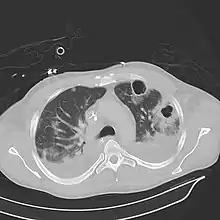

Computed tomography (CT) scan of chest showing bilateral pneumonia with abscesses, effusions, and caverns. 37-year-old male.

Lung abscesses are often on one side and single involving posterior segments of the upper lobes and the apical segments of the lower lobes as these areas are gravity dependent when lying down. Presence of air-fluid levels implies rupture into the bronchial tree or rarely growth of gas forming organism.